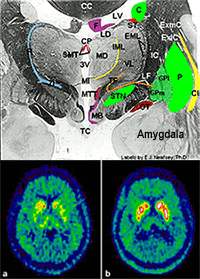

TOP : Highly detailed slide of human brain tissue taken post-mortem.

BOTTOM : F-dopa PET in Parkinson’s disease before (a) and after (b) dopamine cell implantation

SPECT (Single Photon-Emission Computed Tomography) enables doctors to build 3D images of the brain by detecting details about the flow of blood. This shows brain function and is vital for detection of illnesses. This is done by radioactive labelling blood.

PET (Positron emission tomography) scans detect radiation from positrons, and enable a detailed picture of the illness to be constructed. This is vital for patients with brain dysfunction for which the cause has not been determined.